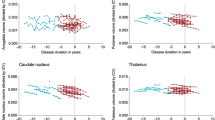

Group analysis of mean volume over all surface-points revealed bilateral global caudate volume decrease in the pmHD group compared to controls (t = 3.4; FDR = 0.005). The effect size of atrophy in the pmHD was large (Cohen’s D = 1.3; the percent of nonoverlap between groups =52 %). Point-wise analysis of local volumes mapped caudate atrophy in pmHD primarily onto medial surface (t > 2.9; FDR < 0.05), with most pronounced changes in anteromedial subdivision (Fig. 2 ; t = 4.5, FDR < 0.001 at the peak) and dorsolateral rim at the head of the caudate (t = 7.0, FDR < 0.001 at the peak). These areas showed even larger effect sizes of atrophy in the pmHD group (anteromedial subdivision: Cohen’s D = 1.8, the nonoverlap between groups =77.4 %; dorsolateral rim: Cohen’s D = 2.7, nonoverlap =82.3 %). Point-wise paired tests revealed no asymmetric atrophy in pmHD (FDR > 0.3).

Group comparison of mean caudate volume (a) and local volumes (b) between patients with pmHD and controls. Caudate atrophy was found in the pmHD group and mapped on the medial surface with the most pronounced change in the region of anteromedial subregion. Gray: non-significant / colors: significant after FDR adjustment for multiple comparisons

In a combined group of patients and controls, global caudate volume positively correlated with scores of global executive function (r = 0.6, FDR <0.05) but not with working memory (r = 0.4; FDR = 0.1). Volume within the area presenting significant group difference showed slightly higher correlations with scores of global executive function (r = 0.8, FDR = 0.001) and working memory (r = 0.5; FDR < 0.05; Fig. 3). In a separate analysis where we performed the same correlation analysis within the pmHD group, however, we found only a trend of correlation for the executive function (r = 0.6, p < 0.01 uncorrected) and no significant correlation for the working memory (r = 0.4, p > 0.2 uncorrected). This was partly due to the small sample size as the effect size of correlation coefficients was high. Point-wise analyses of local volume localized significant correlations mainly in the anteromedial subdivision.

Association between caudate volume and neurocognitive function. a. Within the area showing the significance in the group comparison, we correlated averaged volume and neurocognitive scores. We performed this correlation analysis while correcting for the covariate effect of the group using a linear model in order to remove a possible bias due to the skewness by group differences. Significant correlation was found for both executive function and working memory. b. Point-wise correlation analysis found the significance primarily mapped on the anteromedial subregion (FDR < 0.05)

In patients, global caudate volume did not correlate significantly with disease burden (r = −0.4, FDR = 0.2). Caudate volume within the area presenting significant group difference, however, was negatively correlated with disease burden (r = −0.7; FDR = 0.01; Fig. 4). Splitting our pmHD patients into a low-burden group (n = 7) and a high-burden group (n = 7) and testing their difference in volume, we found a significant difference (t = 3.2; FDR < 0.01).

Association between caudate volume and genetic disease burden. a Within the area showing the significance in the group comparison (Fig. 2), we correlated averaged volume and CAPs. Larger disease burden was significantly associated with smaller caudate volume (r = 0.7; FDR < 0.01). b We split our pmHD patients into a low-burden group (n = 7) and a high-burden group (n = 7) and tested their difference in volume: We found a significant difference (t = 3.2; FDR < 0.01)